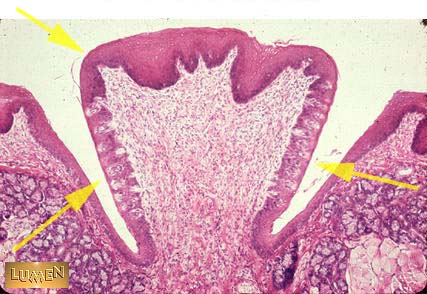

Identify this structure.

Circumvallate papilla